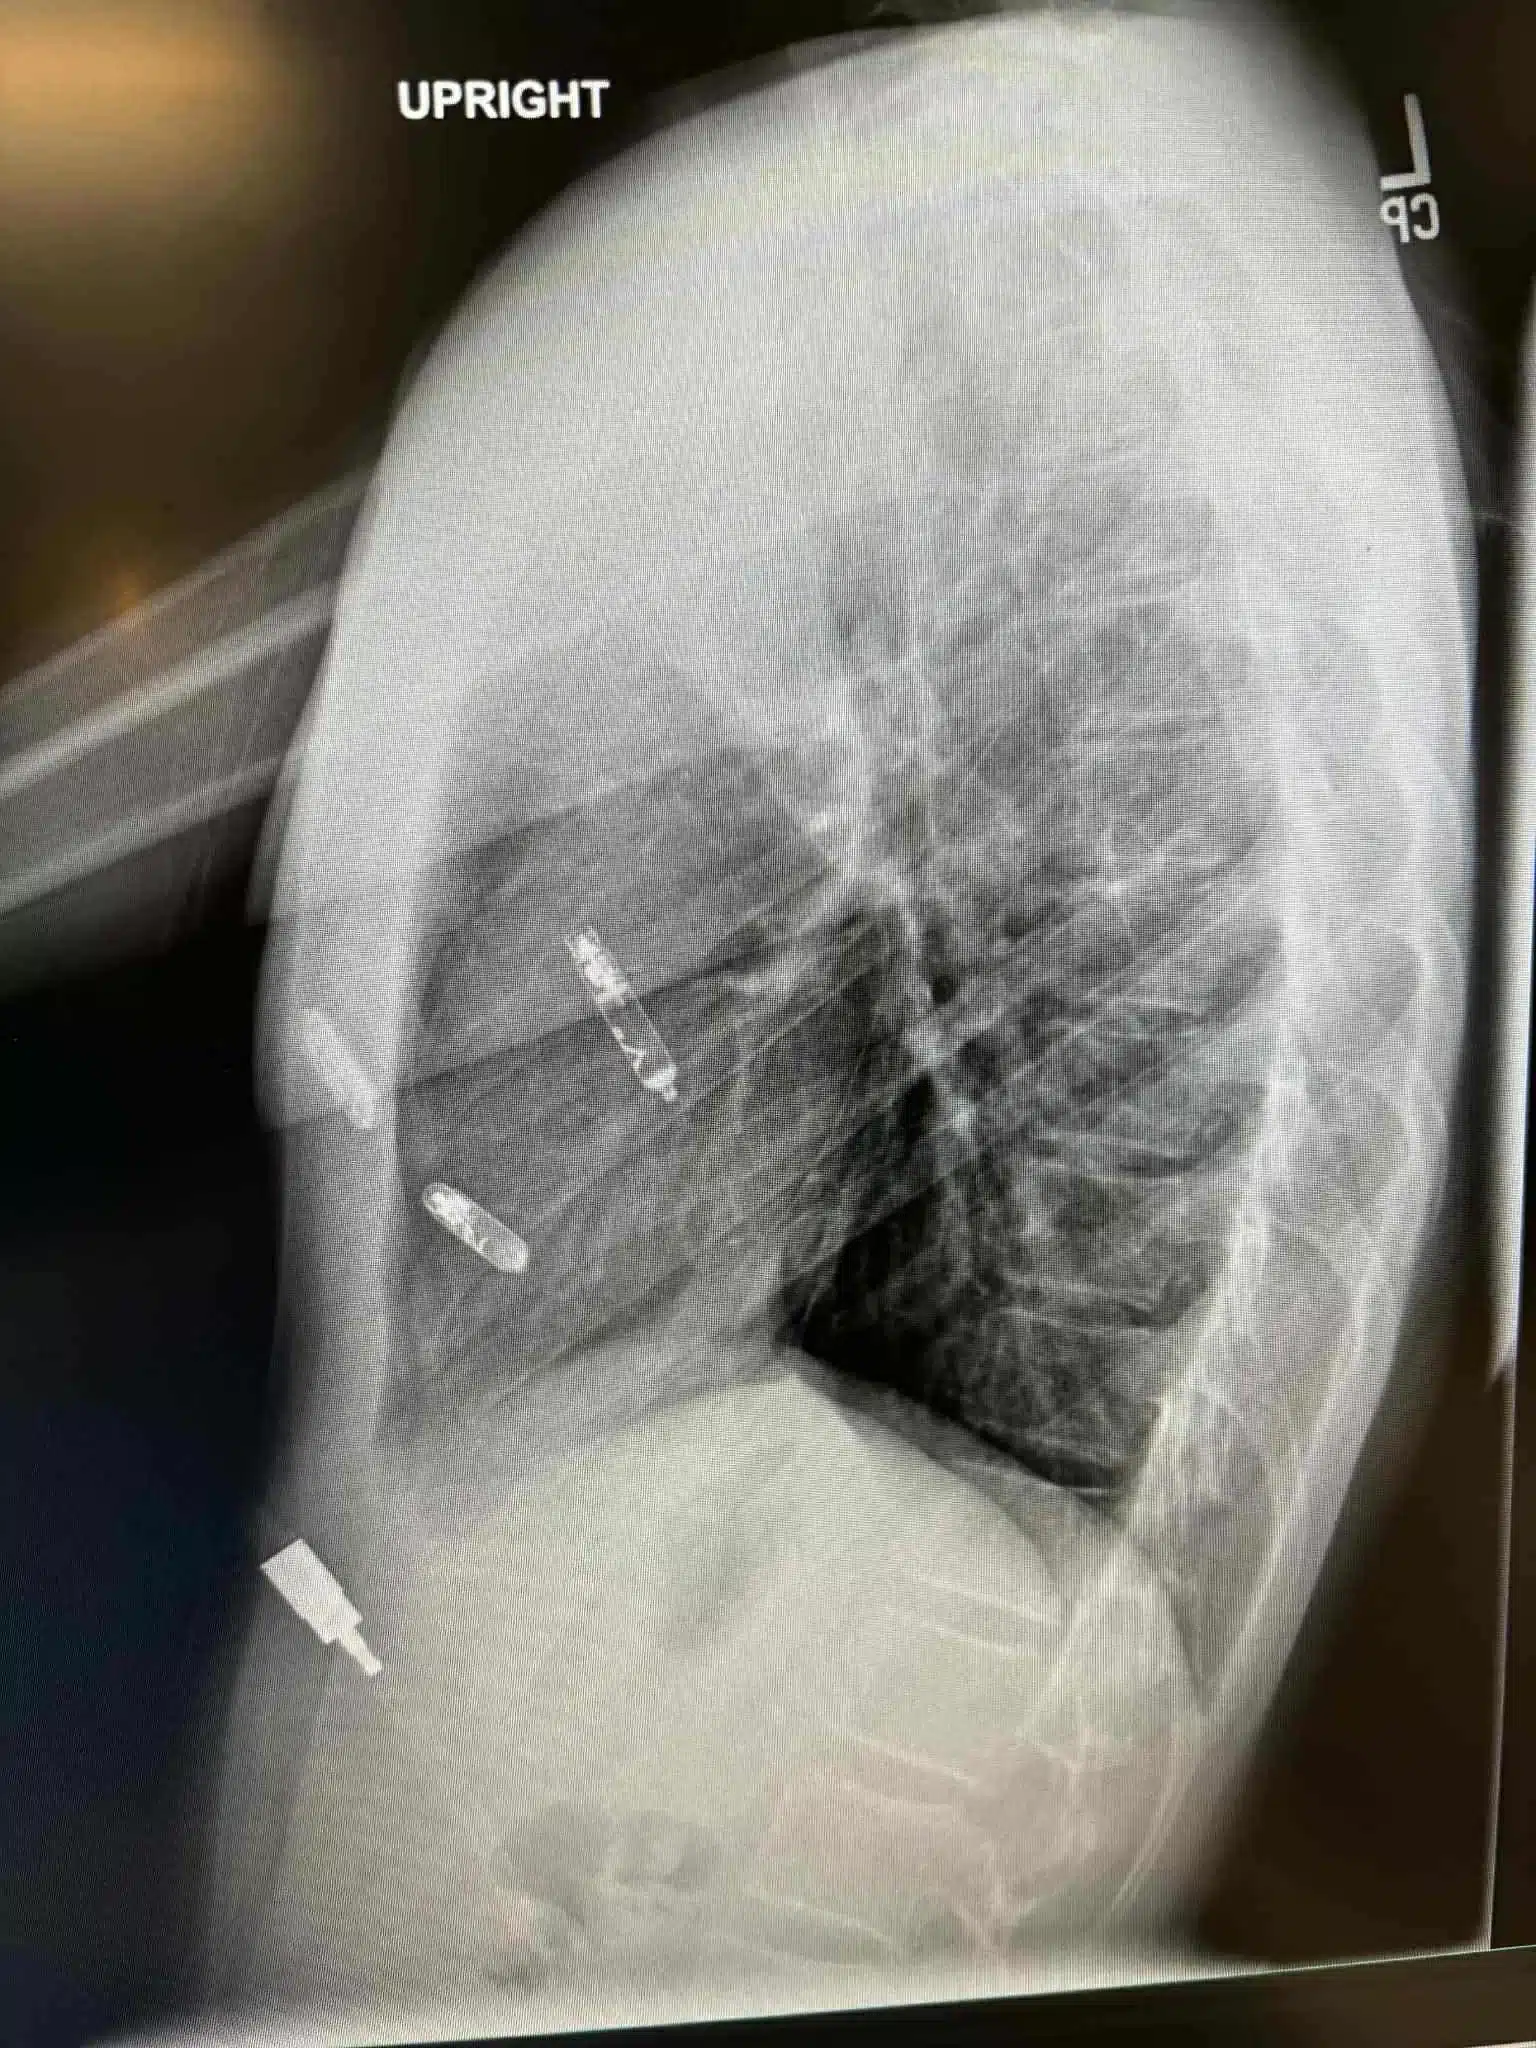

Prije par dana je u američkoj saveznoj državi Floridi izvedena revolucionarna kardiohirurška intervencija koja će ući u medicinsku historiju. Naša Mostarka, dr. Svjetlana Tišma-Dupanović, kardiologinja i pedijatrica, uspješno je pacijentu ugradila dvokomorni pejsmejker direktno u srčane šupljine — u pretkomoru i komoru — koji sinhronizovano stimulišu pravilan rad srca.

Ovo je prva takva operacija izvedena na Floridi, a ujedno predstavlja veliki napredak u liječenju bolesti srca, posebno za pacijente sa poremećajima srčanog ritma i slabijom pumpnom funkcijom srca.

Tradicionalni pejsmejkeri postavljaju se ispod kože grudnog koša, a žice prolaze kroz vene do srca. Nova tehnologija, koju je primijenila dr. Tišma-Dupanović, omogućava direktnu ugradnju uređaja unutar srca — bez žica koje prolaze kroz krvne sudove.

Ovaj dvokomorni (biventričularni) pejsmejker sinhronizuje rad pretkomora i komora, čime se postiže pravilniji ritam i veća efikasnost pumpanja krvi.

U medicinskoj terminologiji, ovakav zahvat spada u “srčanu resinkronizacijsku terapiju” (Cardiac Resynchronization Therapy – CRT), koja koristi više stimulacijskih tačaka za postizanje optimalne kontrakcije srčanog mišića.